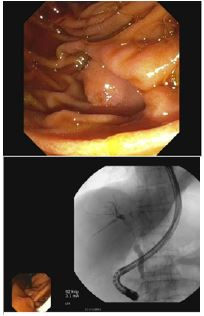

The gastroenterology service was consulted on hospital day 3 for evaluation of cirrhosis and new-onset obstructive jaundice. By this time, the patient’s abdominal pain had resolved, and his conjugated bilirubin had fallen to 2.3 mg/dL, indicating a possible passed stone. Magnetic Resonance Cholangiopancreatography (MRCP) was ordered for further workup of the liver mass and revealed an ill-defined, hypoenhancing mass at the liver hilum, with isolated left intrahepatic biliary dilatation and lobar atrophy (Figure 1).

The enhancement characteristics and location were most suspicious for cholangiocarcinoma. The patient was discharged from the hospital and scheduled for Endoscopic Retrograde Cholangiopancreatography (ERCP) the following week. The patient underwent ERCP with Endoscopic Ultrasound (EUS) which demonstrated a 3 cm intraductal hilar mass extending to the right hepatic duct (Figures 2 & 3).

Figure 1: Hypoenhancing mass measuring 32.7 mm at the liver hilum.

Figure 2 and 3: Presence of 3 cm intraductal hilar mass with positioning shown in reference to the abdomen